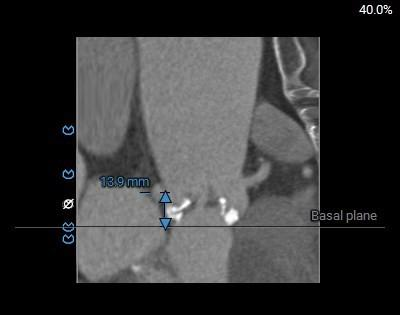

瓣环角度及弓角弓距

◇ 主动脉瓣环水平夹角52°,非横位心,主动脉弓角度较锐(43°)及弓距偏短;